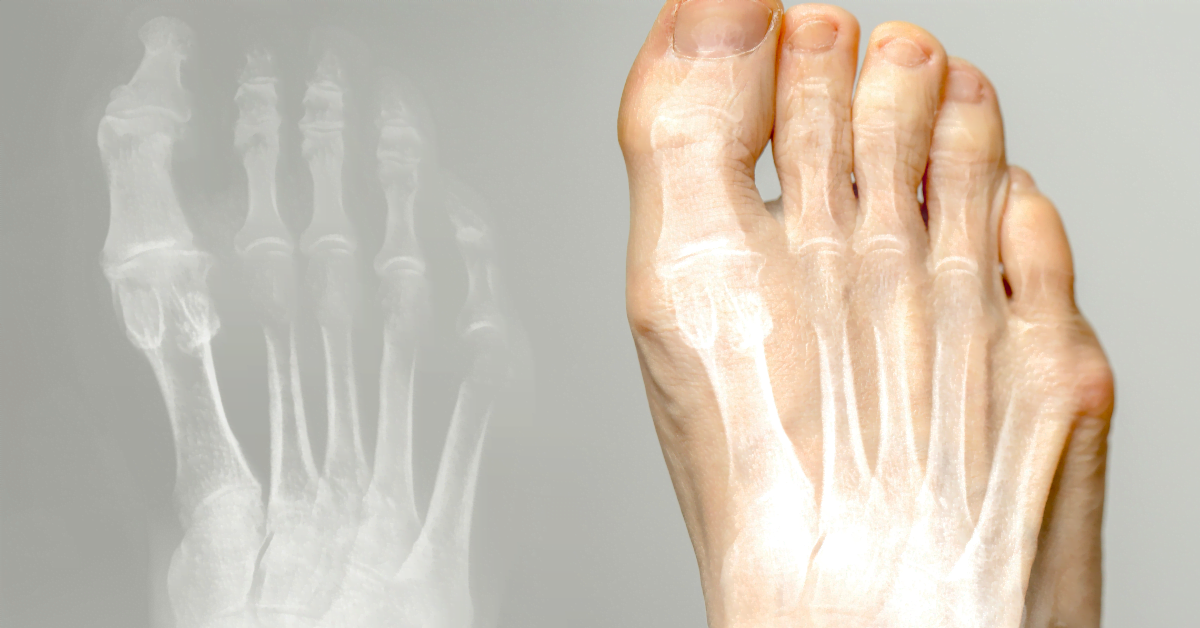

Hallux valgus (Ballenzeh) ist eine Erkrankung, bei der die Großzehe nach innen zeigt und eine Beule an der Basis bildet. Es kann Schmerzen und Unbehagen verursachen. Hier erfahren Sie Ursachen, Behandlung und Vorbeugung.

Die Großzehe biegt sich zu den anderen Zehen hin, wodurch eine Fußbeule entsteht. Ursachen: enge Schuhe, hohe Absätze, Vererbung, Plattfüße oder Arthritis. Schlechte Schuhe verursachen Druck und Reibung, was zu Schleimbeutelentzündungen führen kann.

Beule an der Basis der Großzehe, Schmerzen beim Tragen von Schuhen, Rötung und Schwellung. Brennendes Gefühl, Schwierigkeiten beim Gehen. Manchmal Arthrose in der Großzehe.

Hallux valgus ist eine Fehlstellung der großen Zehe nach innen, mit einem Höcker an der Basis. Oft verursacht durch enge Schuhe, hohe Absätze oder Vererbung. Kann Schmerzen und Schleimbeutelentzündung verursachen.